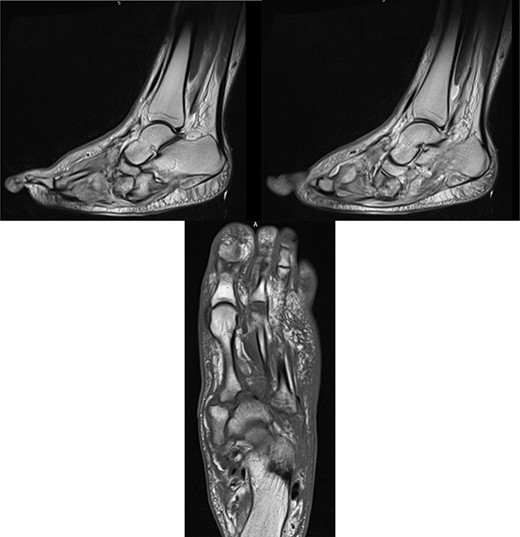

At this presentation, plain film X-ray revealed complete fracture dislocations of the second to fifth tarsometatarsal joints, involving the lateral, middle and medial cuneiform bones of the left mid-foot (Lisfranc fracture dislocations; Fig. 3). This was correlated with bone CT (computed tomography) and MR (magnetic resonance) imaging, with interval changes noted to be of rapid onset (Fig. 4).

MR images, correlating plain film findings of acute mid-foot destructive changes; typical ‘rocker bottom’ appearance of plantar aspect of foot is seen.